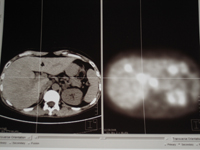

PET TDM